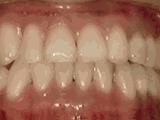

3、牙齿拥挤,个别牙异位,牙弓狭窄,导致局部牙齿重叠生长,两侧各拔牙一颗后,经过矫正是变成这样的~